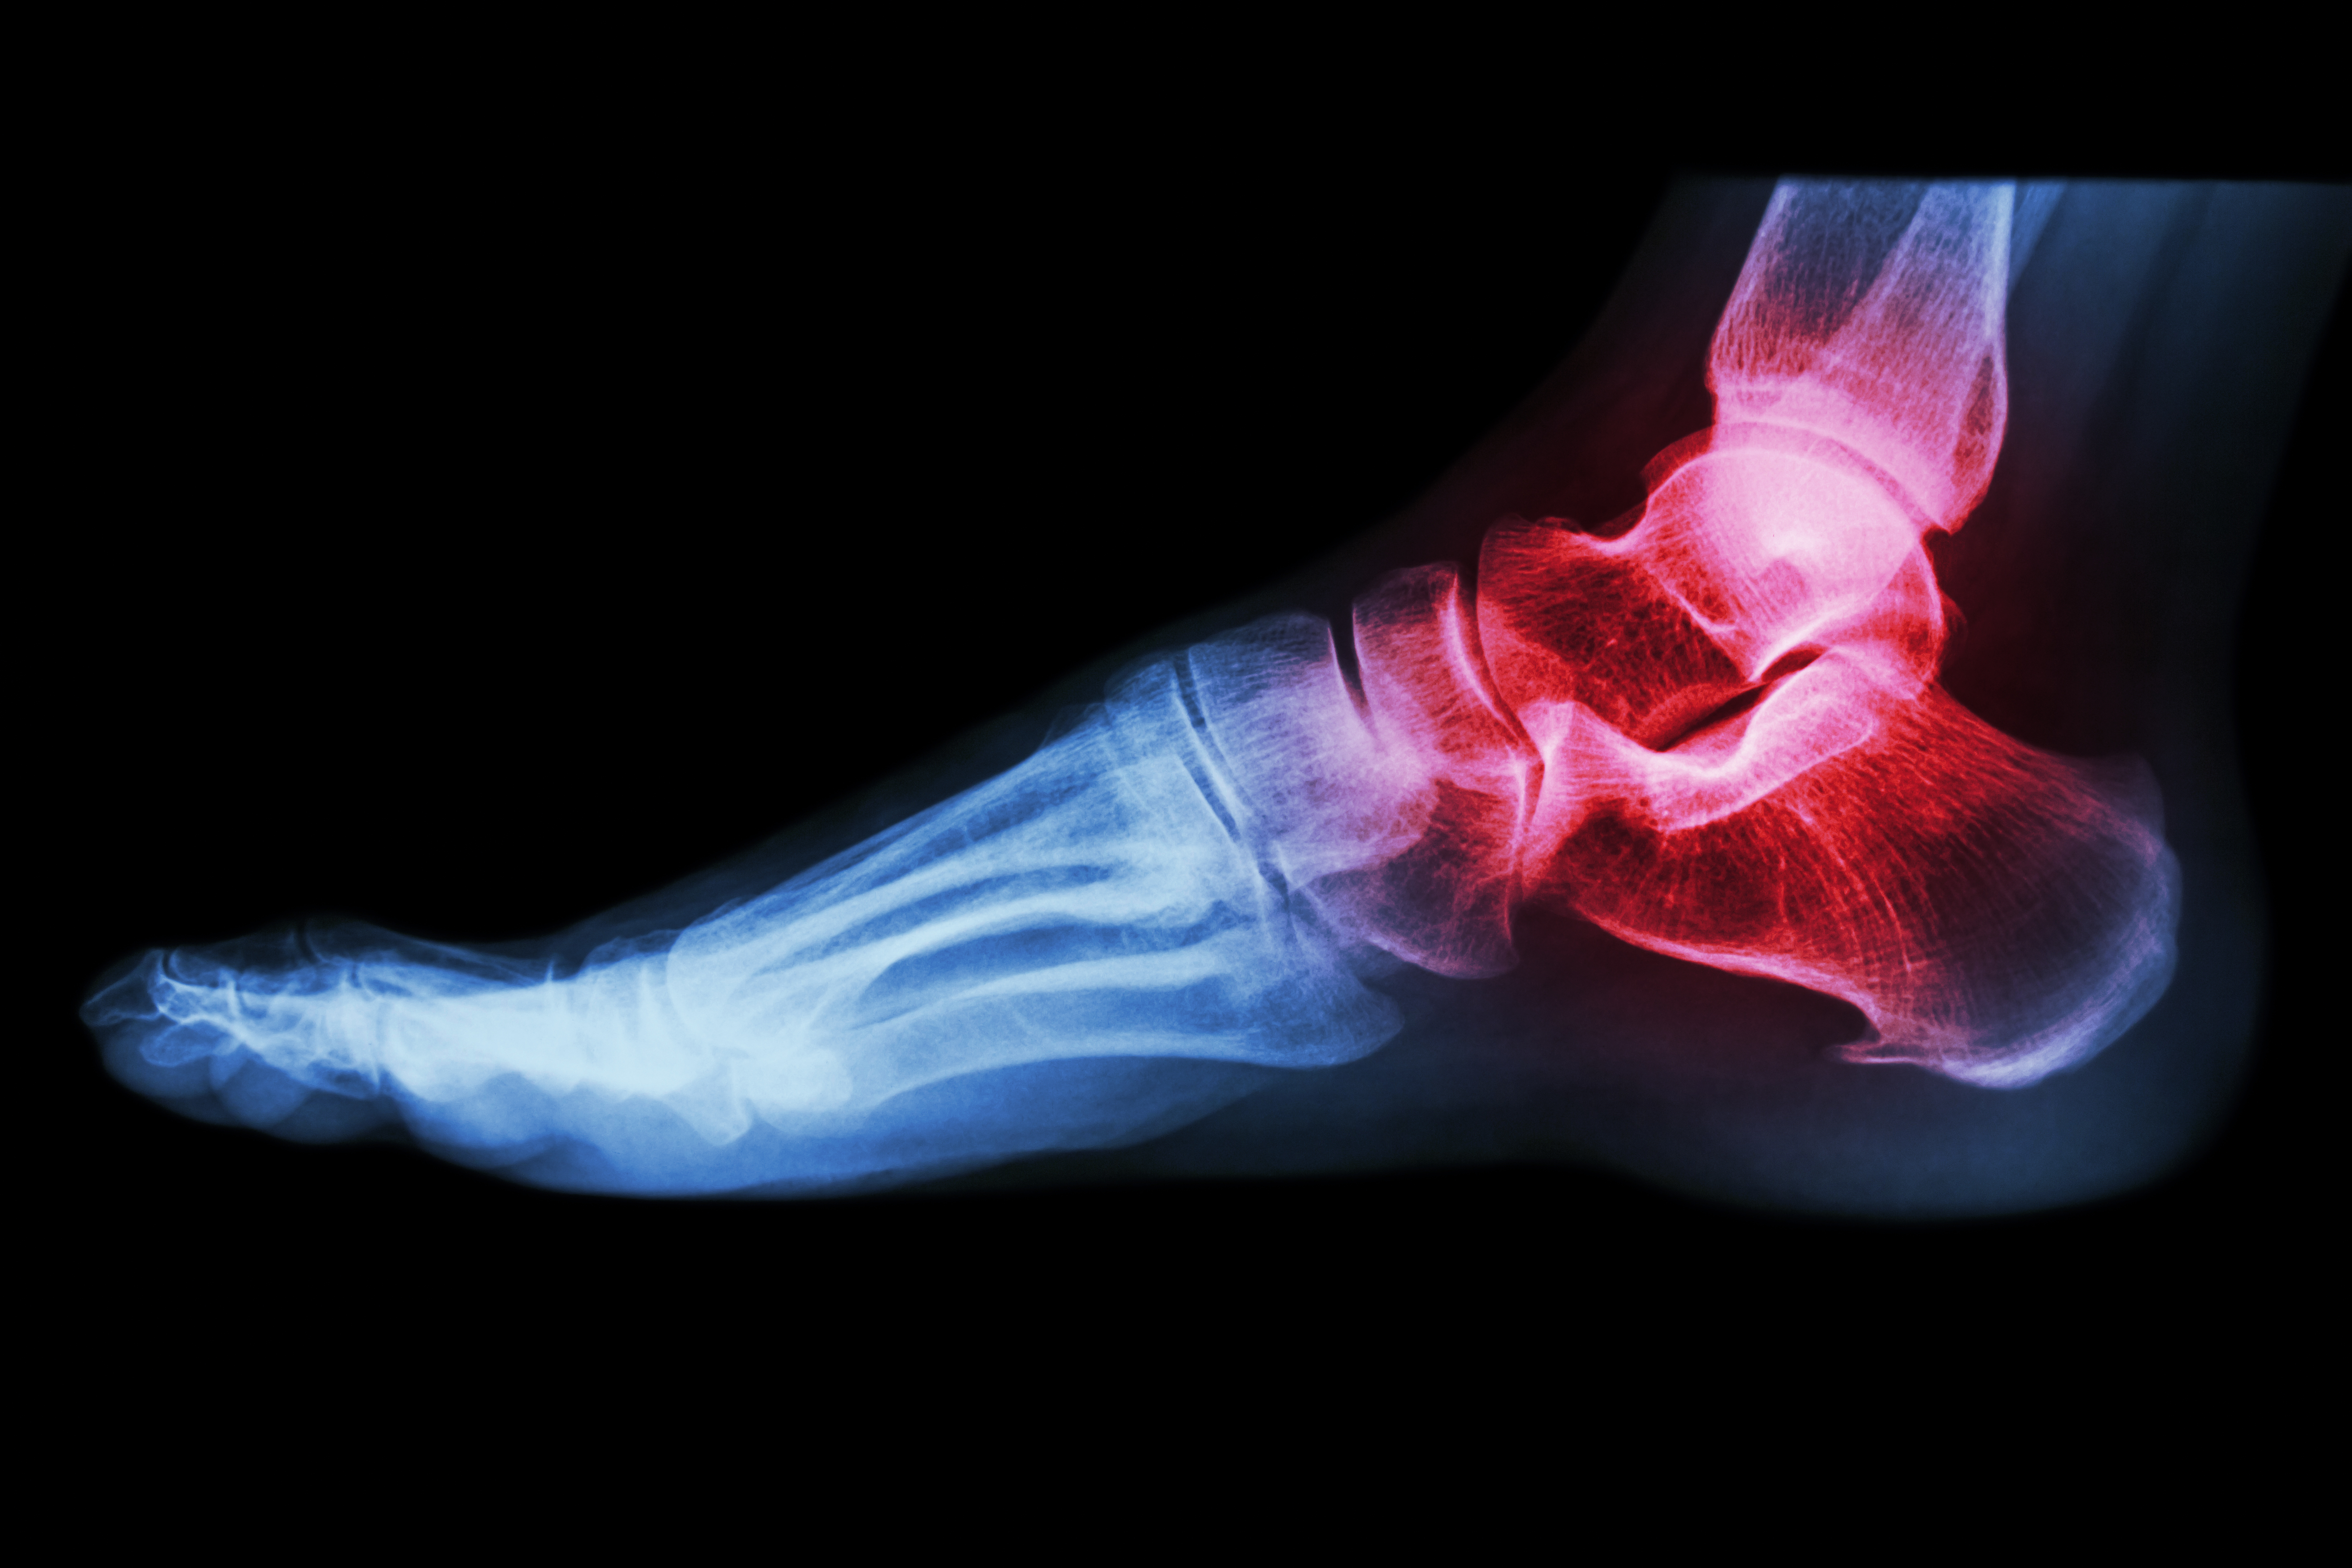

- Fish oil: If you have inflammatory arthritis (red, swollen joints, as in rheumatoid arthritis) add fish oil (1 teaspoon or 3 capsules 2-3 times a day for 6 weeks, then once a day).